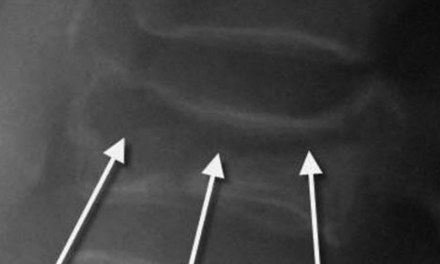

1. The Pseudofracture Appearance of Uncovertebral Arthrosis

In the lateral view of figure 1, note the horizontal radiolucent line through C5 and C6. This finding is often mistaken for a fracture on radiographs. The AP radiograph nicely demonstrates uncinate process hypertrophy at C6 and C7. The degenerative hypertrophy of the uncinate processes causes an abnormal pseudoarthrosis to form between the uncinate process below and the inferior vertebral body above. This pseudoarthrosis results in the horizontal radiolucency seen traversing the vertebral body.